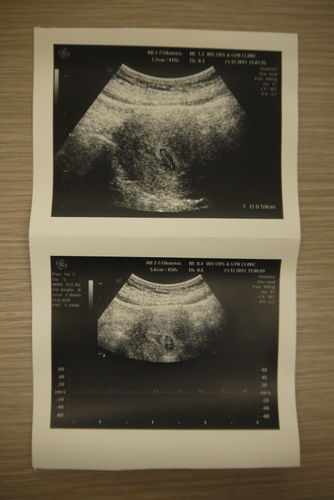

12/23 7WEEK 吳婦產科-吳瑞文

告訴醫生一直持續出血,醫生照超音波發現子宮內膜不穩定而且有在收縮,

因此開了3天分安胎藥,一天吃兩次,回家走路散步逛街都禁止,盡量躺或坐著休息

小朋友已經有0.59CM,心跳正常

12/25 7WEEK3D 吳婦產科-吳瑞文

早上起床坐在沙發上忽然感覺有血流出來,大概護墊的量,鮮血,衝去婦產科看診

醫生判斷子宮內膜已經有穩定了,但是還是幫我打了安胎針+安胎藥改一天4次

說小朋友心跳有一百多了,看起來很穩定不需要太擔心,多休息就好(我都已經臥床3天了QQ)

12/30 8WEEK 吳婦產科-吳瑞文

寶寶已經有1.25CM,醫生說看起來很OK,但以防萬一還是開安胎藥讓我吃到9WEEK